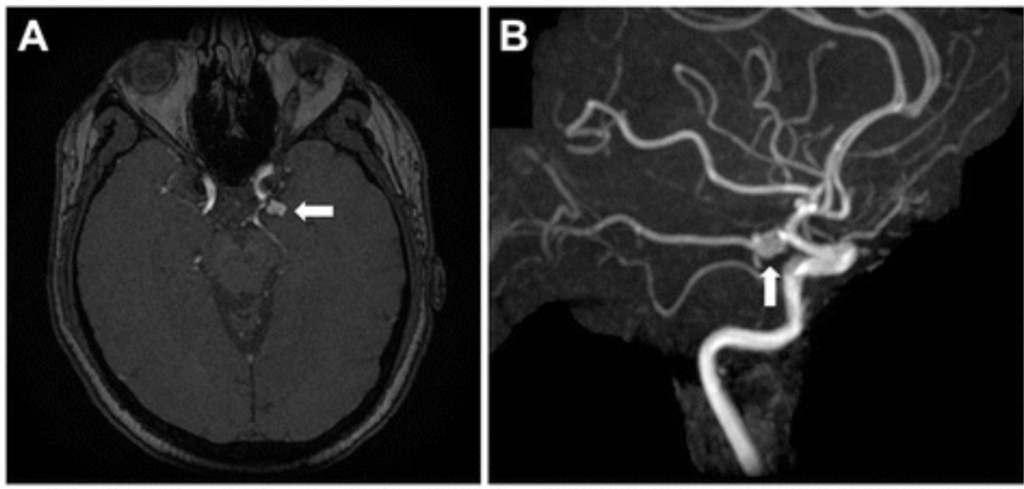

Como é feito o diagnóstico do aneurisma cerebral?

O aneurisma cerebral não é diagnosticado apenas pela consulta médica ou pelo exame físico e neurológico.

Ele é identificado por exames de imagem, que permitem ver os vasos do cérebro.

Na maioria das vezes, o aneurisma é descoberto por acaso, quando a pessoa faz um exame por outro motivo, como dor de cabeça, tontura ou investigação de esquecimento.

Os exames mais usados são:

- Angiotomografia arterial de vasos do crânio (Angio-TC)

É uma tomografia com contraste que mostra os vasos do cérebro.

É um exame rápido e bastante utilizado para investigar aneurismas.

- Angiorressonância arterial de crânio (Angio-RM)

É feita com ressonância magnética e também permite ver os vasos cerebrais.

Não usa radiação e, em muitos casos, pode ser feita sem contraste.

- 3. Angiografia Cerebral (ou arteriografia)

Em situações específicas, pode ser indicado um exame mais detalhado, chamado angiografia cerebral.

Esse exame é mais invasivo e costuma ser reservado para casos em que é preciso avaliar melhor o aneurisma ou planejar um tratamento.

Depois que o aneurisma é identificado, o médico avalia os exames para decidir se o aneurisma pode apenas ser acompanhado com consultas e exames regulares ou se precisa de algum tipo de tratamento.